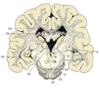

Label the diagram

Label the diagram (MAJOR STRUCTURES ONLY!)